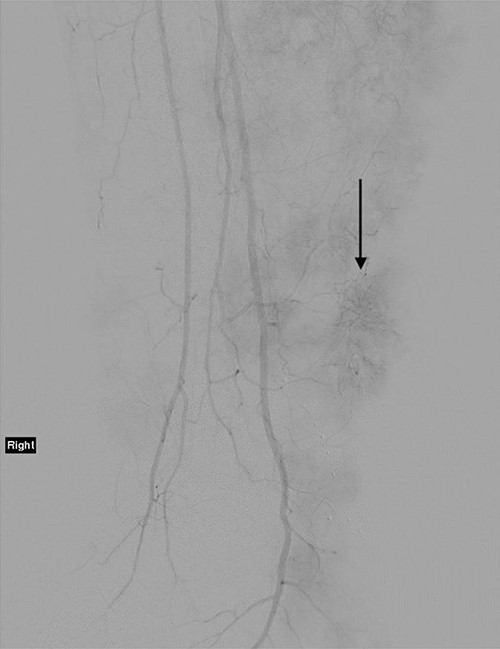

The technique of ILI has been described previously. It is a minimally invasive procedure that involves isolating the blood supply of a limb in order to control the delivery of chemotherapy drugs into it and to avoid systemic drug toxicity. A tourniquet is applied to the proximal limb to quarantine the limb blood supply after the arterial and venous catheters have been placed to circulate high doses of chemotherapy throughout the limb for 30 minutes [9]. Figure 2 demonstrates a post-catheter placement digital subtraction angiography image of the diseased limb, showing the significant vascularity of the lesions that makes ILI an effective treatment by delivering cytotoxic chemotherapy in high doses directly to tumour deposits. The patient progressed well in the immediate post-operative period.

Angiogram of the right leg, showing the significant neoangiogenesis present in the large tumour masses; the arrow indicates one of the highly vascular tumour deposits.